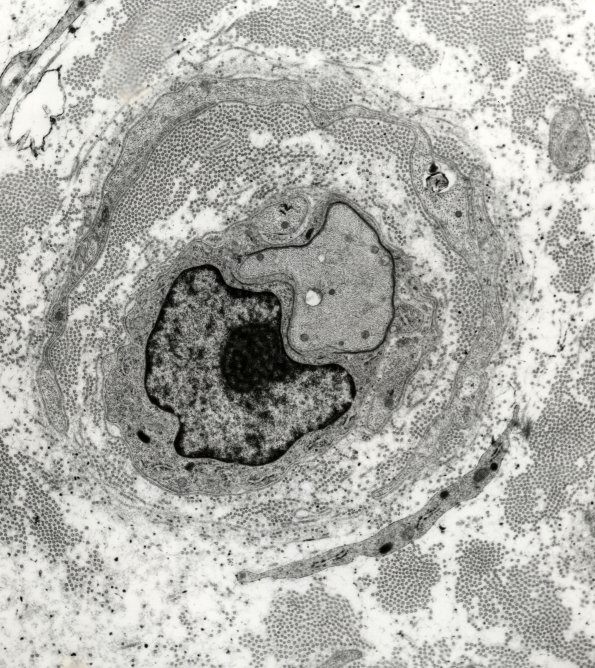

Early remyelination is a typical response to macrophage-mediated demyelination. (electron micrographs)